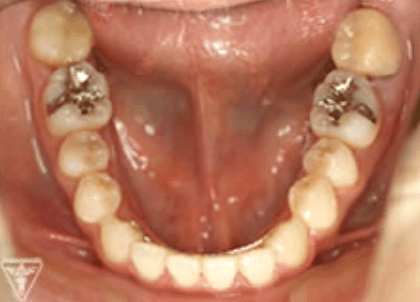

20代女性:オープンバイト(開咬)をゴムメタルにて矯正治療したケース

症状

オープンバイトは、上下の歯を噛み合わせた時に奥歯は噛んでも前歯が噛まない歯列不正の1つです。

原因には遺伝的なものや指しゃぶり 舌癖 口呼吸など様々なものが上げられます。

前歯で噛み切れない、正しく発音しにくいなどの機能障害をはじめ、顎関節症・歯周疾患を併発する可能性があります。

治療前、装置装着直後